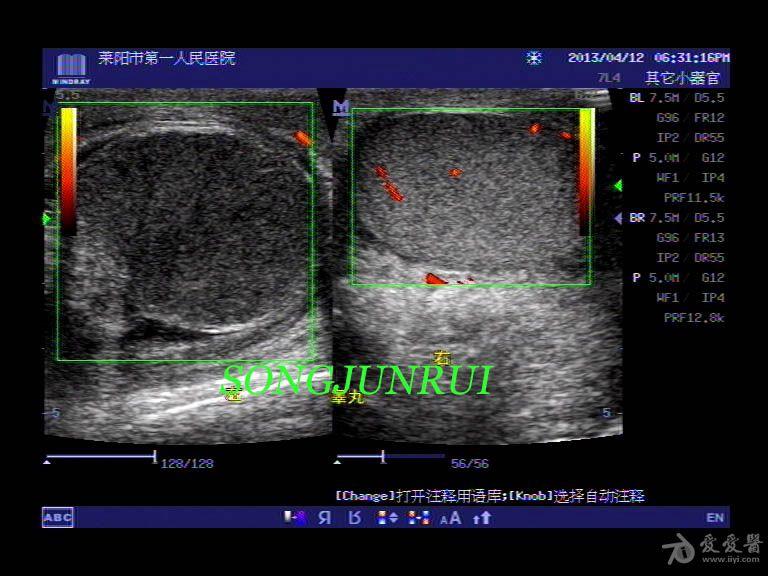

大家看个睾丸扭转的

图片尺寸768x576